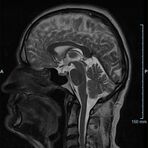

Im Magnetresonanztomographen liegt die zu untersuchende Person in einem starken, homogenen Magnetfeld. Dieses Magnetfeld bewirkt eine gemeinsame Ausrichtung der Wasserstoffprotonen im Körper entlang der Längsachse des Magnetfeldes. Wird nun diesen Teilchen Energie in Form von Radiowellen in einer genau abgegrenzten Frequenz zugeführt, so werden sie aus ihrer ursprünglichen Orientierung abgelenkt.

Die zugeführte Energie wird in gewebespezifischer Weise wieder abgegeben. Ein hochempfindliches Computersystem misst die unterschiedliche Energieabgabe und setzt sie in Bildinformationen um. Jede Körperregion kann somit durch Schnittbilder in allen Raumebenen oder durch dreidimensionale Rekonstruktionen mit einem exzellenten Weichteilkontrast dargestellt werden. Es besteht keine Belastung durch Röntgenstrahlen.

Kopf

• akute Schlaganfalldiagnostik und chronische Durchblutungsstörungen

• entzündliche Prozesse des Gehirns oder der Gesichtsweichteile

• Tumore, ggf. mit Spektroskopie

• Abklärung Schwindel, zentrale Sehstörung, Kopfschmerz

• Metastasenverdacht